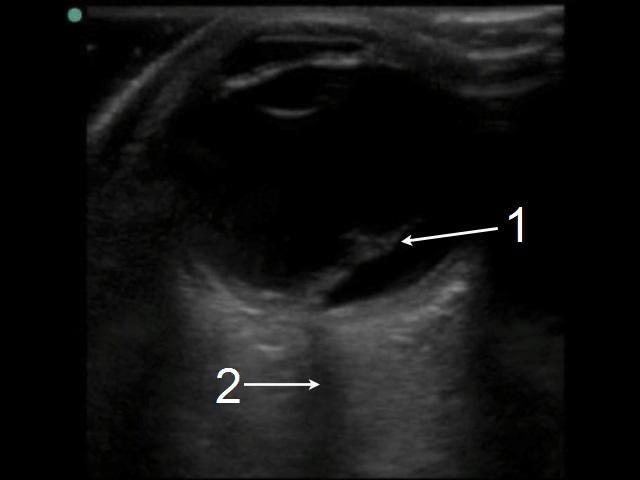

Ocular Retinal Detachment – Macula Involvement Image

Retinal Detachment (RD)

Optic Nerve